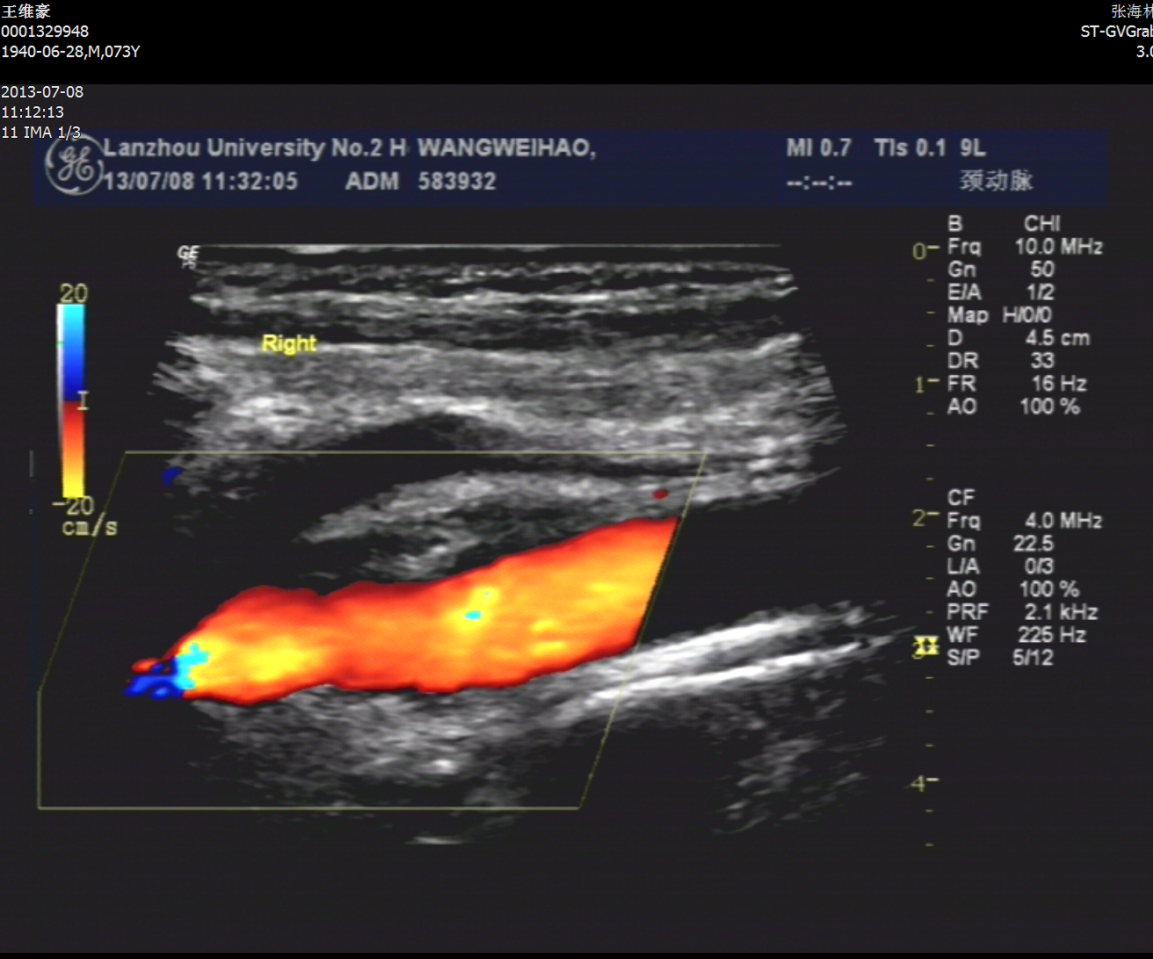

术后颈动脉超声

术后